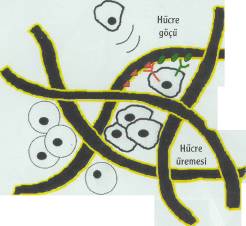

damarlarının organik bir iskeleti oluşturuluyor. Bu iskeleti oluşturduktan sonraki aşamaysa hücrelerin oluşturulması. Damar iskeleti çevresine yerleştirilen karaciğer hücreleri, belirli büyüme faktörleri yardımıyla çoğalarak organın kalın etli kısmını oluşturuyorlar. Bir sonraki aşamaysa damarın oluşturulması. Bunun için süngerimsi yapıda olan PLGA içine damar hücreleri enjekte ediliyor. İskelet, hücrelerin çoğalması için gerekli büyüme faktörlerini ve besin maddelerini içeriyor. Damar hücreleri iskelet boyunca ilerleyerek karaciğer hücrelerine yapışıyor. Burada çoğalan damar hücreleri, iskelet çevresinde birleşerek tam bir damar yapısı oluşturuyorlar. PLGA iskelet birkaç ay içinde kendiliğinden eriyerek geride karaciğer hücreleri ve içinde damarları olan yapay bir organ bırakıyor. Bu şekilde oluşturulan yapay karaciğer hayvanlarda denendi. Oldukça iyi kan akımının sağlandığı bu organlarda dışarı kan sızıntısı da gözlenmedi.

Tabii bu teknolojiyi ideal şekle getirmek çok kolay değil. Karaciğer içinde değişik görevleri olan milyonlarca hücre var. Yalnızca bir gram karaciğer dokusunda yaklaşık 100 milyon karaciğer hücresi bulunuyor. Hücrelerin gerekli noktalara yerleştirilmesi ve buradaki konumlarını korumalarının sağlanması oldukça güç. Yapay karaciğer oluşturulmasında karşılaşılan diğer bir güçlükse, organın mikroplardan arındırılması. Yapay organların içine hiçbir mikrobun girmemesi gerekiyor. Bu nedenle, çalışmalarda kullanılan tüm cihaz ve aletlerin steril, yani mikroptan arındırılmış olmaları çok önemli.